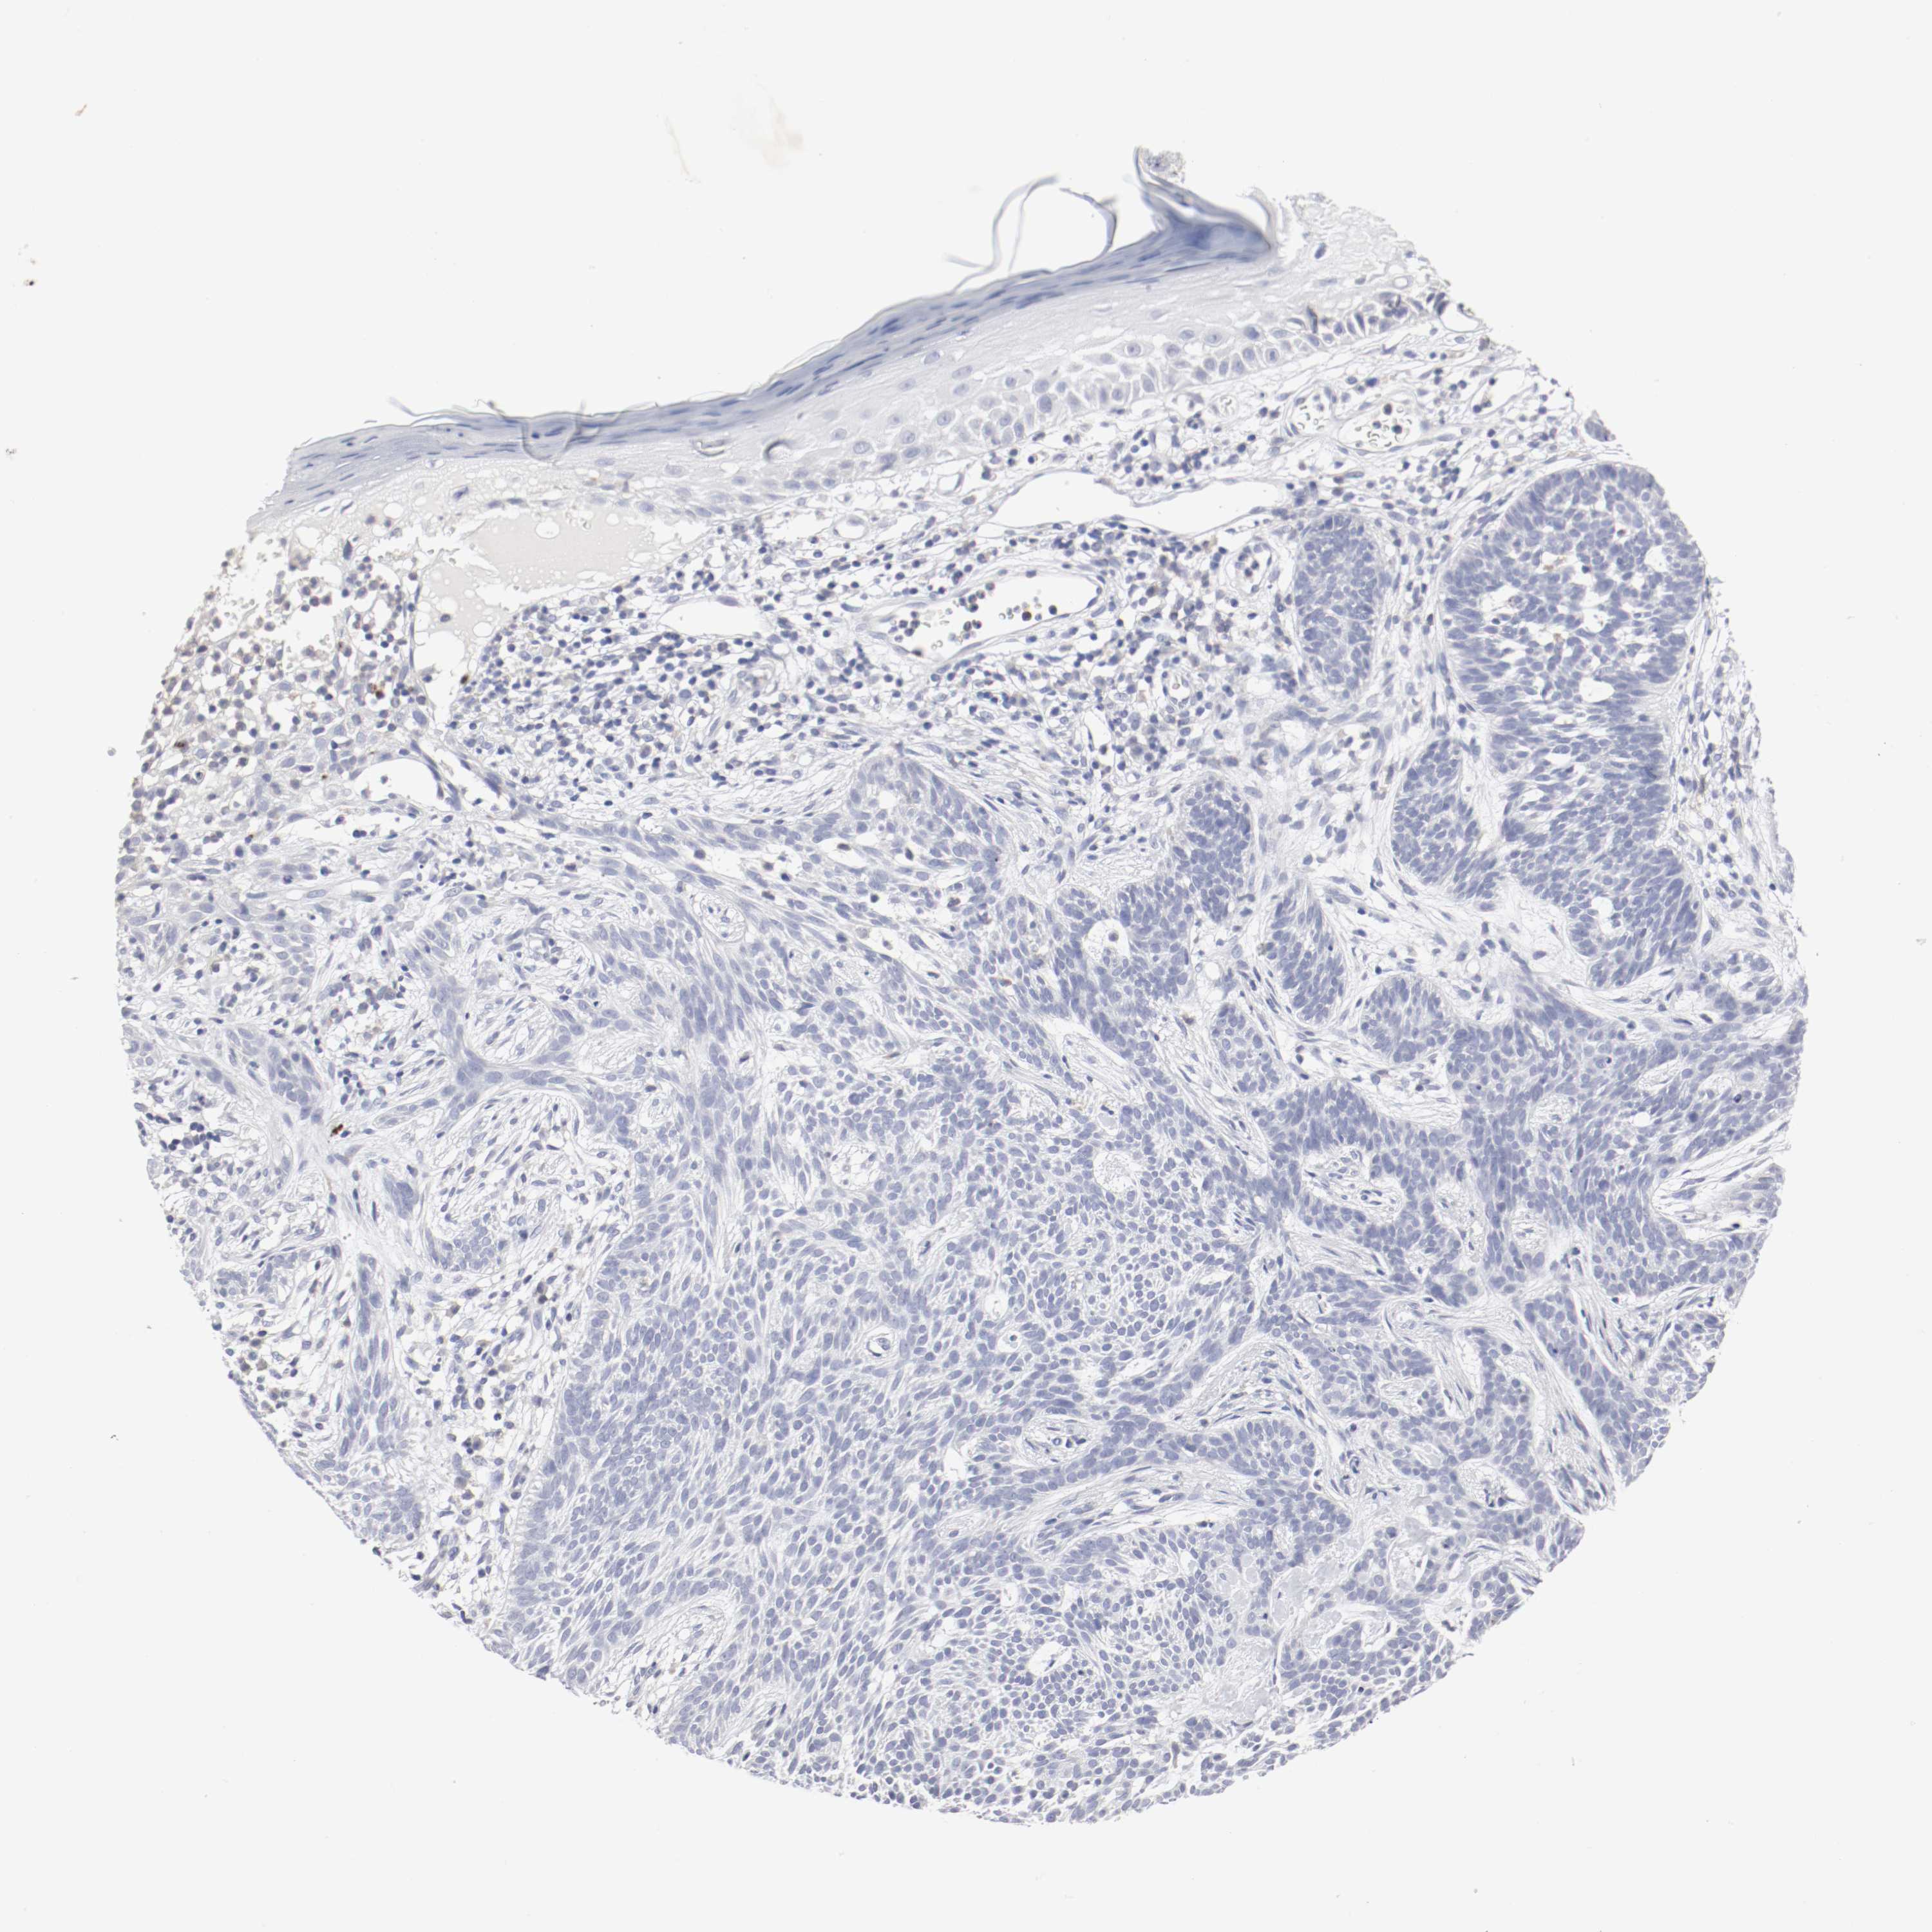

CANCER SKIN CANCER Show tissue menu

Basal cell and squamous cell cancer

SKIN CANCER - Protein expressioni

A mouse-over function shows sample information and annotation data. Click on an image to view it in a full screen mode. Samples can be filtered based on level of antibody staining by selecting one or several of the following categories: high, medium, low and not detected. The assay and annotation is described here.

Each image is clickable and will lead to virtual microscopy that enables deeper exploration of all samples and also displays staining intensity scores, fraction scores and subcellular localization as well as patient and tissue information for each sample.

Antibody CAB004458

Squamous cell carcinoma, NOS

Basal cell carcinoma